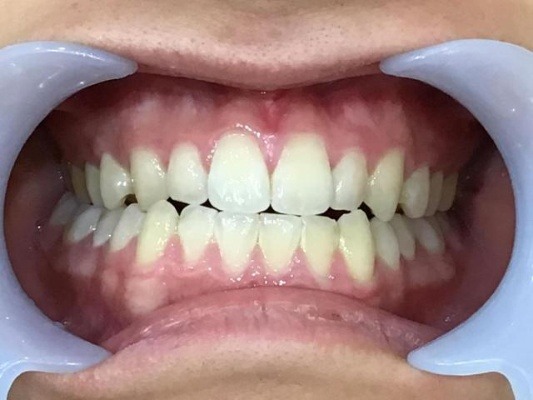

正面

| 治療内容 | インビザライン 全顎 |

| 治療詳細 | 反対咬合や叢生を整えるために、歯の表面にアタッチメント(白い突起)をつけ、IPR(歯と歯の間を削る)を行いました。 また、顎間ゴムと呼ばれる上顎と下顎に渡って引っ掛けるゴムの補助装置も用いて治療を行いました。 |

| 患者情報 | 10代 男性 デンタルモニタリング使用 |

| 主訴 | 下顎が前に出ている(受け口) 歯のがたつき |